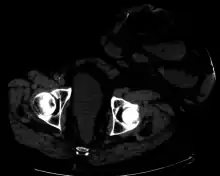

One well-known form of an artificial stoma is a colostomy, which is a surgically created opening in the large intestine that allows the removal of feces out of the body, bypassing the rectum, to drain into a pouch or other collection device. This surgical procedure is invoked usually as a result of and solution to disease in the GIT. The procedure involves bisecting this tube, usually between the later stage of the small intestine (ileum) and the large intestine or colon, hence colostomy, and exiting it from the body in the abdominal region. The point of exiting is what is known as the stoma.

For greatest success and to minimize negative effects, it is preferable to perform this procedure as low down in the tract as possible, as this allows the maximal amount of natural digestion to occur before eliminating fecal matter from the body. The stoma is usually covered with a removable pouching system (adhesive or mechanical) that collects and contains the output for later disposal. Modern pouching systems enable most individuals to resume normal activities and lifestyles after surgery, often with no outward physical evidence of the stoma or its pouching system.